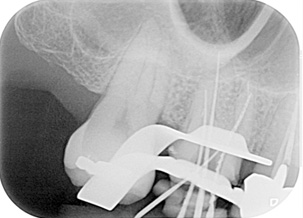

多根根管治療

治療後